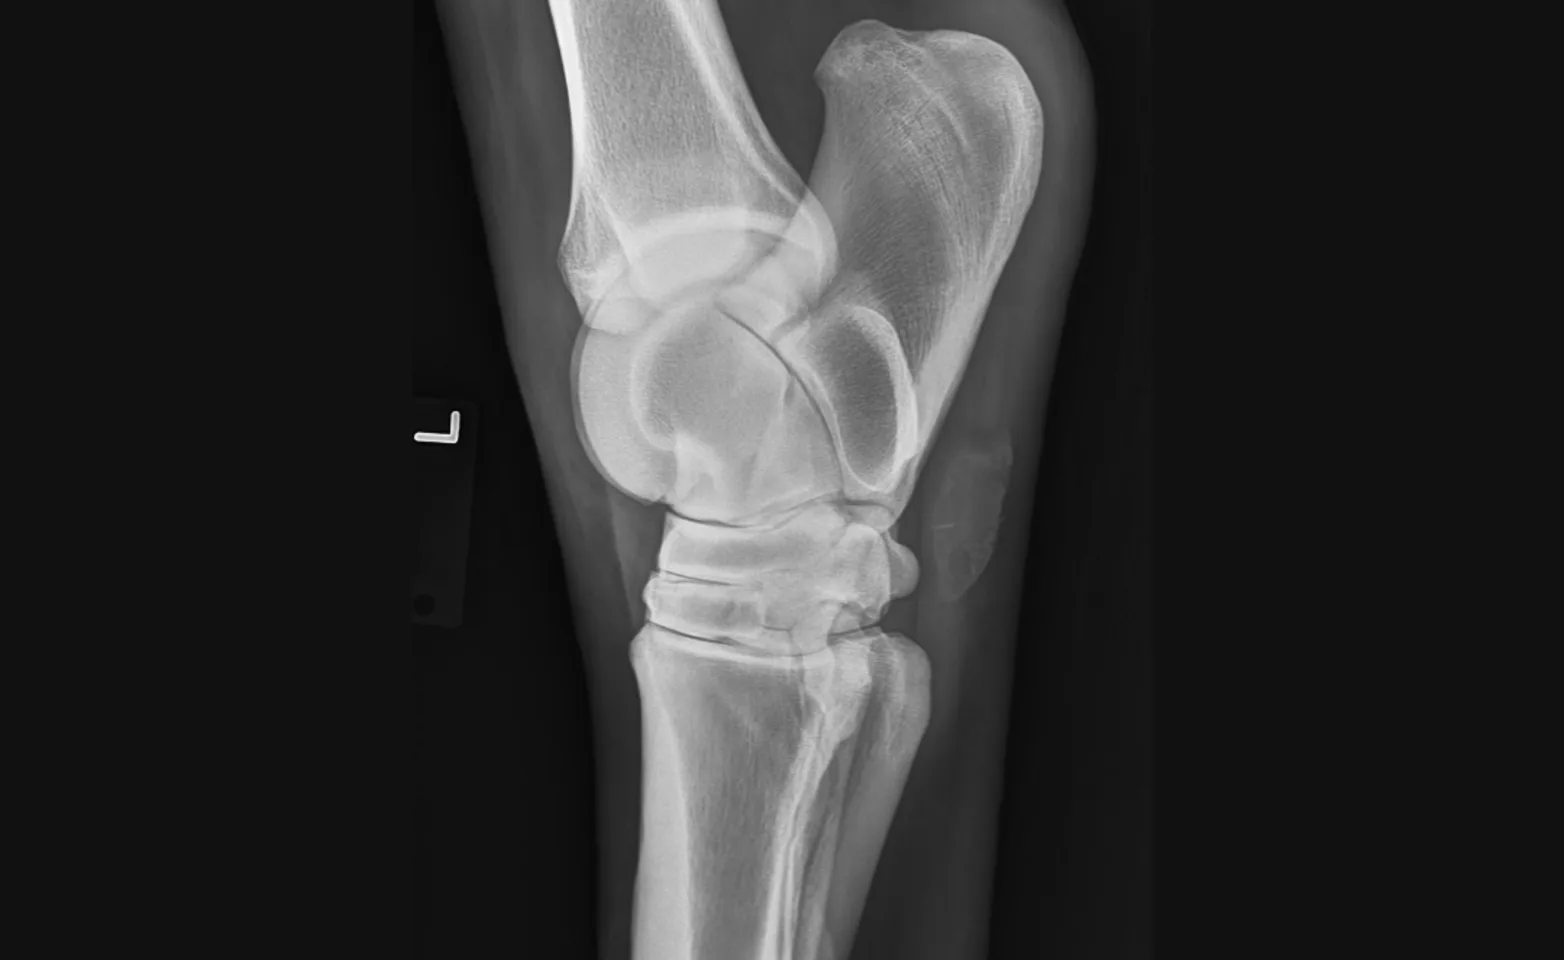

Digital radiography allows for evaluation of bones, both normal and abnormal, which can be used in several different types of appointments. Images are high quality and can be viewed immediately to provide timely recommendations. Wounds and (some) foreign objects can be evaluated and located. Intra-operative radiographs ensure proper placement of orthopedic screws and plates.

Arthritis and lameness

Fractures